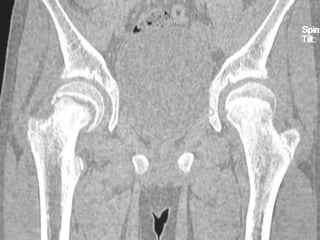

 CT SCAN-

Accurately measures extent of epiphyseal displacement & angulation.